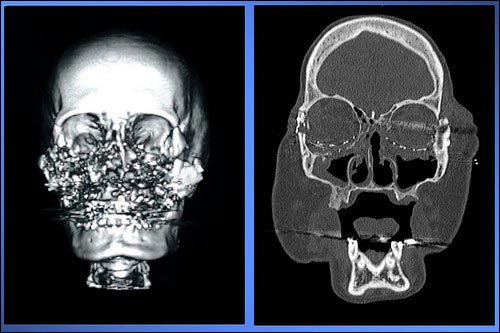

وخلال الجراحة الماراثونية، أعاد فريق الجراحين تشكيل وجه الواهب ليتلائم والمريضة، وقاموا بوصل الأنسجة، والعظام، والأوعية الدموية والخلايا العصبية، وتركيب الأنف، والأجفان السفلية وأعلى الشفة، وملء الشواغر في وجه كالي.

قبل زراعة الوجه

بعد زراعة الوجه